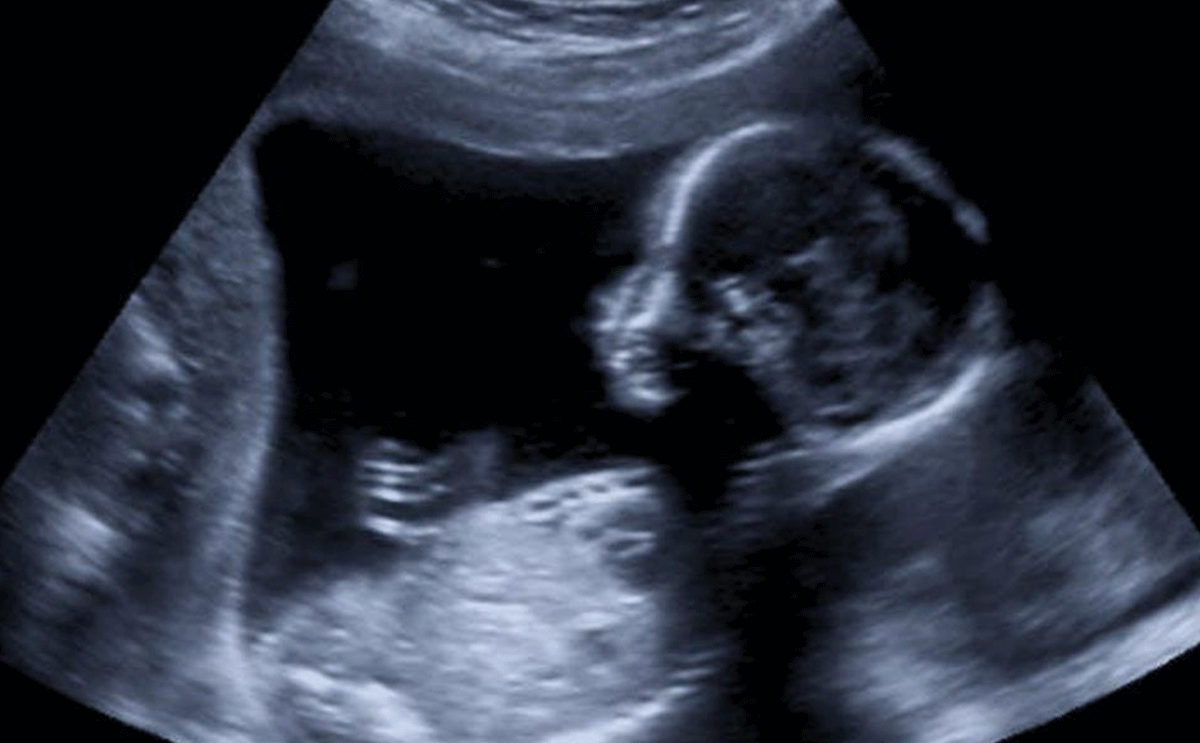

في اي اسبوع يظهر نبض الجنين في السونار

أكثر ما يشغل تفكير المرأة عندما تصبح حامل وخصوصاً في الأشهر الأولى من حملها، هو سماع صوت دقات قلب طفلها، لأنه سيطمئنها على صحة الطفل وسلامته. لذلك تتساءل الحوامل في أي اسبوع يظهر نبض الجنين في السونار؟

السؤال هنا هو إذاً متى يبان نبض الجنينمن خلال السونار؟ الموجات فوق الصوتية أو السونوغرام، المعروفة بالسونار هي الطريقة الأكثر دقة والأكثر استخدامًا من قبل الأطباء لفحص نبضات قلب الجنين. بشكل عام، خلال الأسبوع الـ 5.5 و الـ 6.5 يكون أبكر وقت يستطيع الطبيب رصد نبضات قلب الجنين التي ستظهر للمرة الأولى من خلال الأدوات الطبية. إذاً، حوالى ستة أسابيع يمكنك سماع نبض قلب طفلك الصغير باستخدام (الموجات فوق الصوتية) السونار. خلال هذه المرحلة المبكرة، يجب أن يكون معدل نبضات قلب الجنين حوالي 100 نبضة في الدقيقة.

مع تقدمك في أيام الحمل، يجب أن ترتفع نبضات الطفل كي تصل إلى 120 و الـ 160 دقة في الدقيقة الواحدة، وإذا لم تصل نبضات قلب الجنين الى هذا المعدل من الممكن أن يكون دليلاً على مشاكل في قلب الطفل يحب أن تقومي بمراجعة طبيبك المختص في الحال، لتجنب أي مضاعفات خطيرة على صحة الطفل.

لكن، في حال لم يستطع الطبيب رصد نبضات الطفل في الأسبوع السادس أو حتى السابع هذا لا يدعو الى القلق، لأنه في بعض الحالات، يتأخر تكون قلب الطفل ما يؤدي الى تأخر القدرة على رصد صوت نبضات قلبه لذلك من الممكن أن تنتظري الى الأسبوع الثامن، التاسع وحتى العاشر وهذا لا يعني أن طفلك في خطر أو يعاني من أي مشكلة، لكنه ليس الوقت المناسب كي يسمع نبض الجنين.